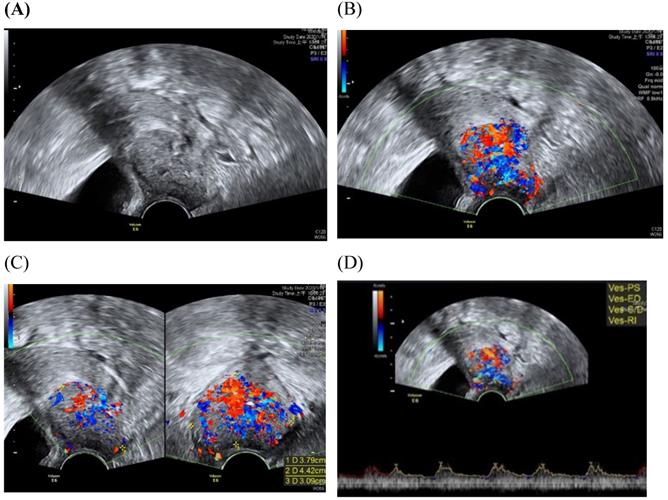

Figure 3

Transvaginall ultrasound image gray scale and color Doppler shows a longitudinal section of the uterus with cervical cancer of the female aged 68-year-old. (A) Gray scale shows cervical mass (B) color Doppler shows abundant blood flow in cervical mass (C) color Doppler (D) color Doppler Blood flow.

Among imaging techniques for the evaluation of cervical cancer, ultrasound is faster, radiation-free, cheaper, noninvasive, no contrast medium required and more widely available than other imaging techniques [13]. Furthermore, advanced technologic developed in the field of ultrasound over the recent decades; image quality were improved. Transvaginal and transrectal high-frequency ultrasound, can give detailed images of the cervical tumor as the probe is positioned close to the tumor [13]. Anatomy features of longitudinal sections of the uterus with normal cervix by (TVUS) examination and transabdominal sonography are shown in Figures 1 and 2. Furthermore, Figure 3 showed vascularity detected by transvaginal Color Doppler in cervical cancer. Ultrasound may provide highly accurate information on detecting tumor presence evaluating local tumor extent if performed by ultrasound-trained gynecologists [6]. The experience of readers is also critical for correct pretreatment staging and assessment of response to treatment [6]. This review article attempted to present the most updated specific applications of ultrasound in cervical cancer.